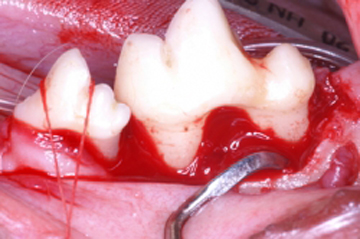

- Amputación radicular

- Hemisección radicular